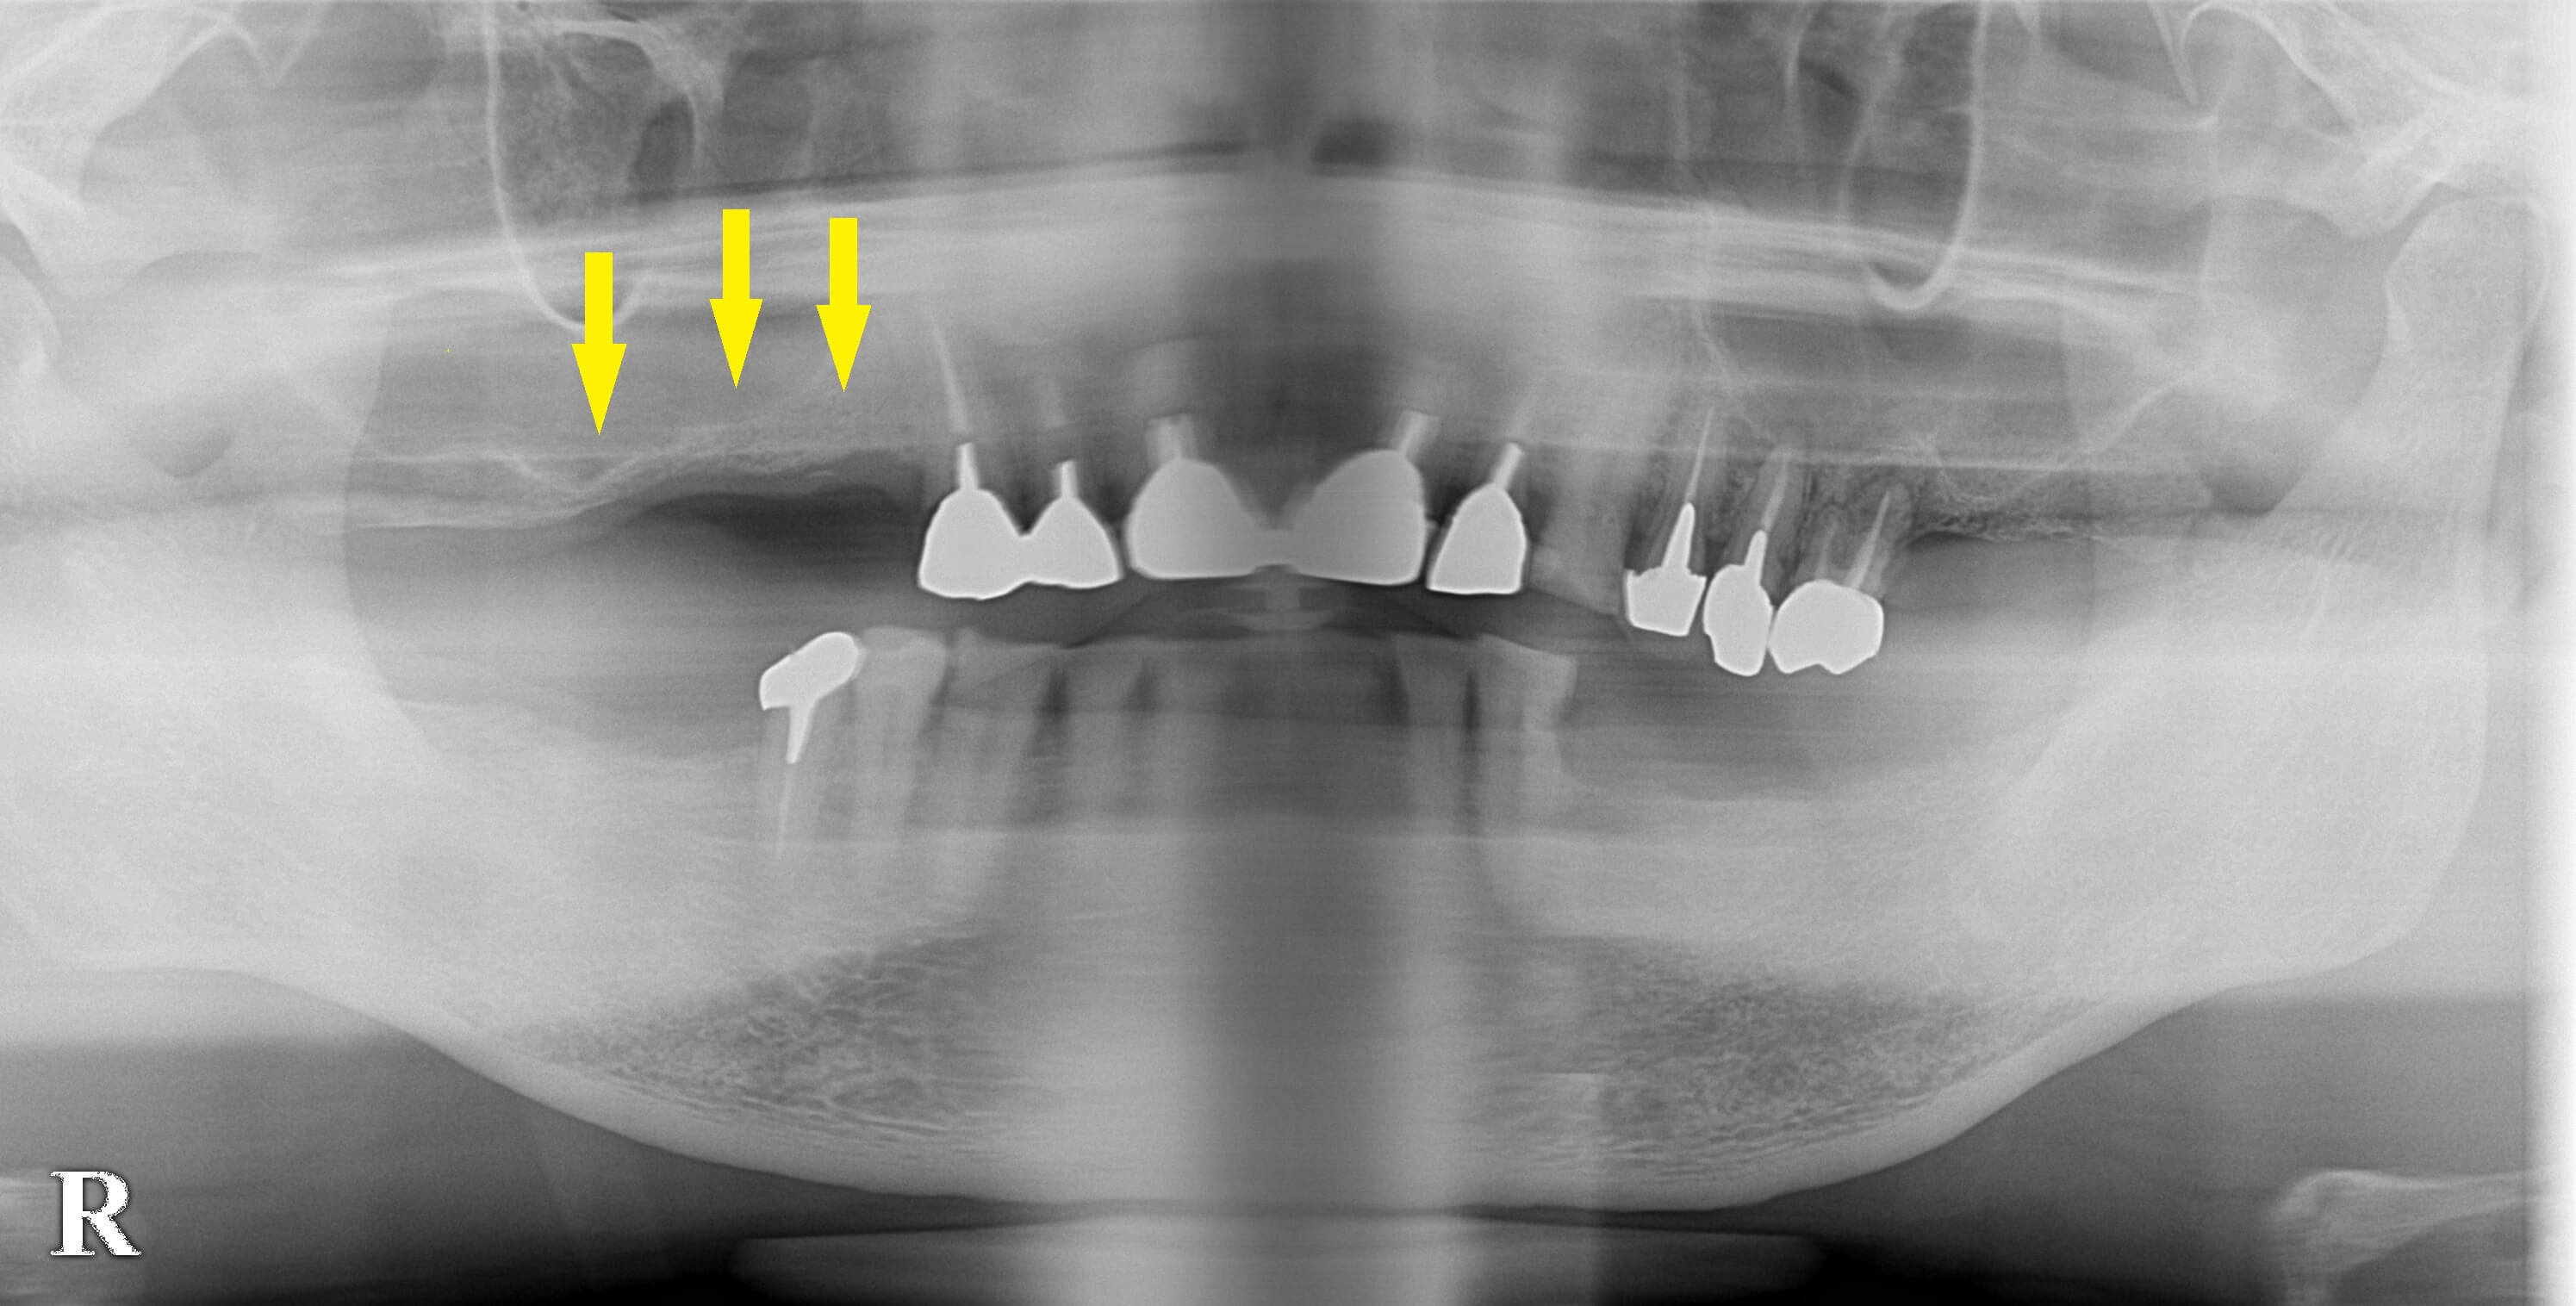

レントゲン写真でも、CTで見ても骨は菲薄で、特に右上顎、第一大臼歯部は、1~2mmほどしかありませんでした。

下の写真、下段の写真が手術後のCTです。

これまでのインプラントよりも、かなり太いインプラントが埋入できています。